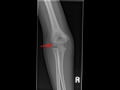

Panner Disease

This is a young patient who presents with lateral elbow pain over the last 3 months. Frontal and lateral radiographs of the elbow were obtained. The frontal radiograph demonstrates an irregular appearance of the capitellum as indicated by the red arrow. The capitellum appears flattened with a mixed lytic and sclerotic appearance. These same findings are also nicely seen on the lateral radiograph as identified by the red arrow. The abnormality involves the entirety of the capitellum. No loose body within the elbow joint is appreciated. These findings are most consistent with an osteochondrosis of the capitellum, also known as Panners Disease. Panners disease most commonly occurs in young patients between the ages of 8-12. It is secondary to overuse, and is commonly seen in children who participate in little league baseball or softball. This osteochondrosis will resolve on its own with rest and symptom management. It is important to distinguish this disease from osteochondritis dessicans of the capitellum, which may also occur in children who play baseball or softball. However, as opposed to Panners disease, osteochondiritis dessicans usually affects older adolescenets, does not involve the entirety of the capitellum, and is associated with loose bodies. It is also not a self-limiting disease process. These clinicial and imaging features help to distinguish the two disease processes.